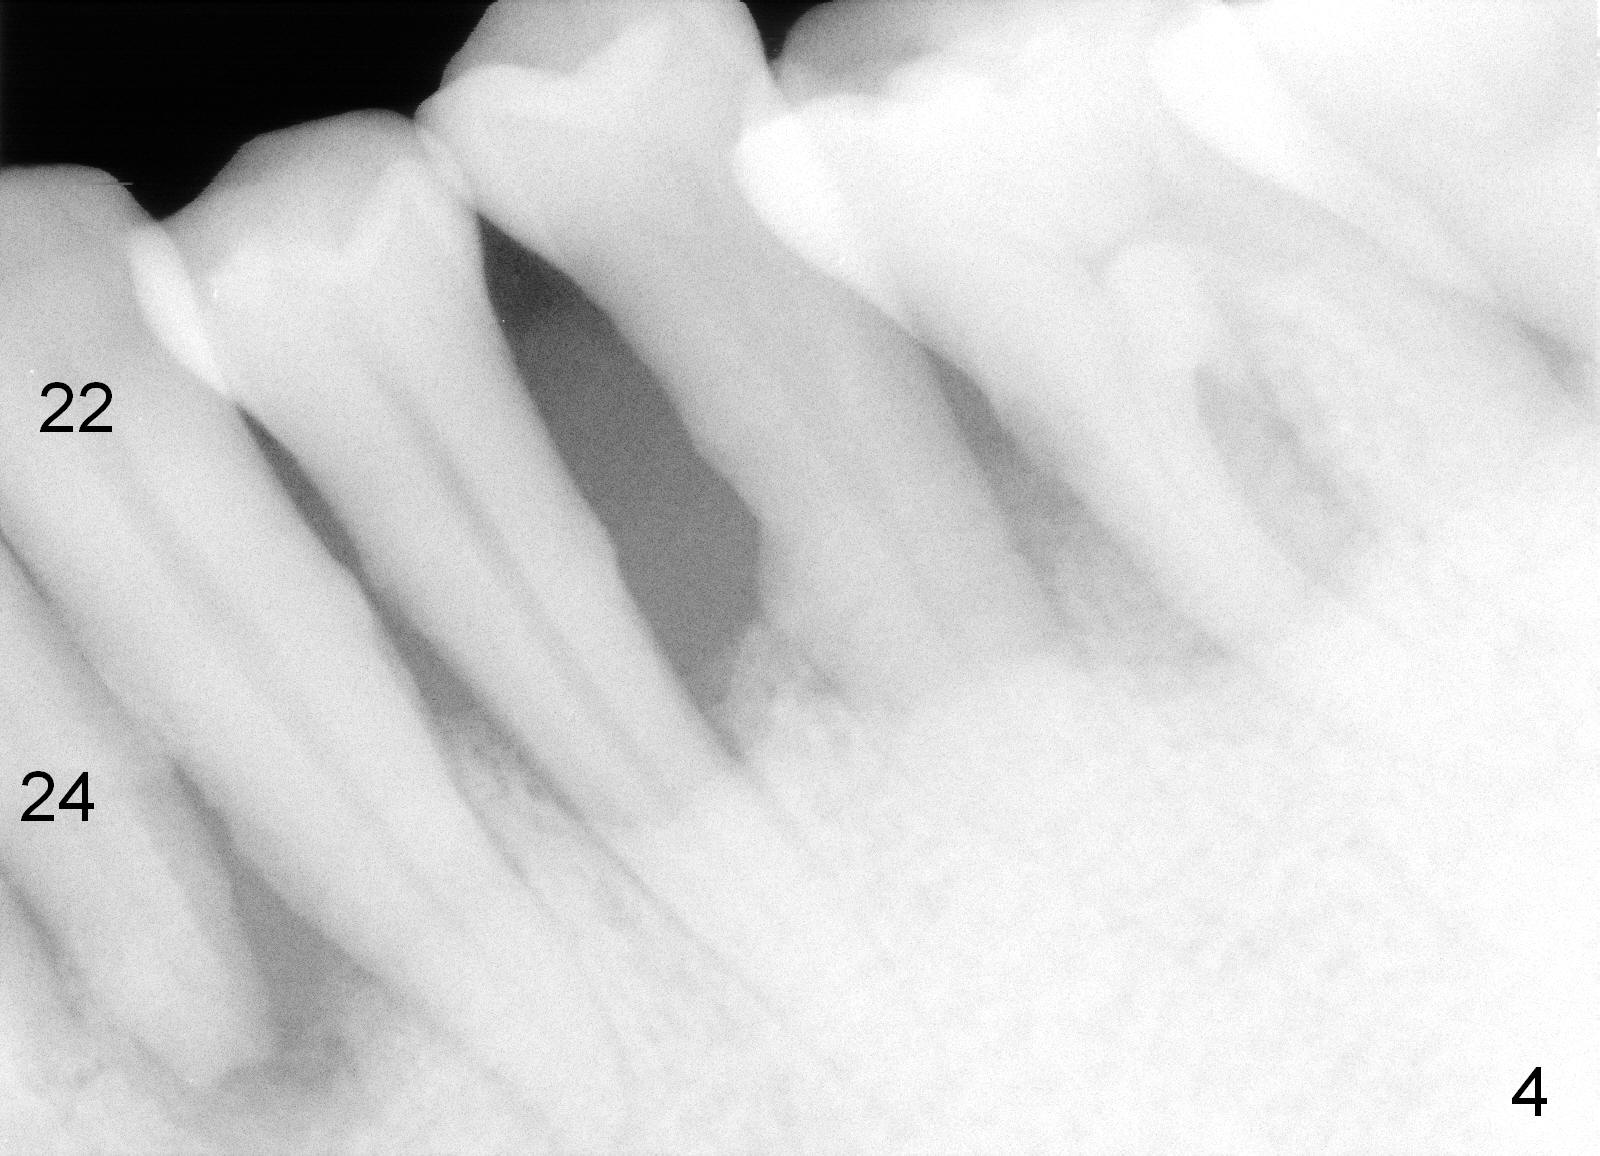

A 62-year-old man (CZ) has severe generalizd chronic periodontitis and occlusal trauma. Full mouth extraction and reconstruction is required. The patient prefers extraction by stage. The lower anterior segment reconstruction is our first treatment: from #22-28. The tooth #28 is exfoliated now (Fig.1 (full mouth X-ray was taken 4 years ago), 5). There are 3 incisors left. Two-piece implants are going to be placed for the canines and premolar, while 2 of 1 piece implants in the incisor sockets (treated with Metronidazole with Epinephrine gauze) for a bridge (Fig.2). Straight 1 piece 3 mm implants are routinely placed, whereas angled or 2.5 mm ones are backup. Two of 1.2 mm pilot drills and 3 of marked parallel pins may be needed.